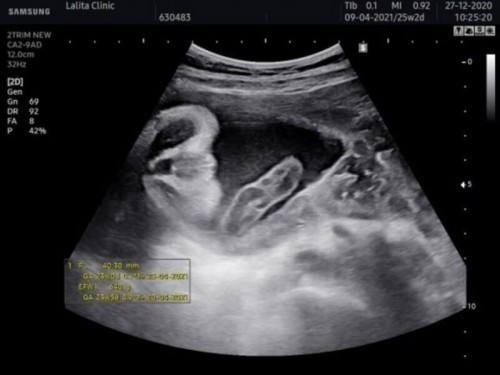

สอบถามค่ะ แม่ๆคะรูปส่วนนี้ คือรูปตรงไหนของน้องค่ะ อวัยวะเพศหรือป่าว ช่วยๆดูและเม้นหน่อยจ้า ดูไม่ค่อยเป็นจ้า เห็นหมอบอกว่าเป็นเพศผญ.100% มั่นใจมากเพราะน้องห้อยขาอยู่ แต่ลืมถามหมอว่าเราต้องดูรูปอันไหน5555#ขอคำแนะนำหน่อยค่ะ #ขอบคุณกับคำตอบจ้า